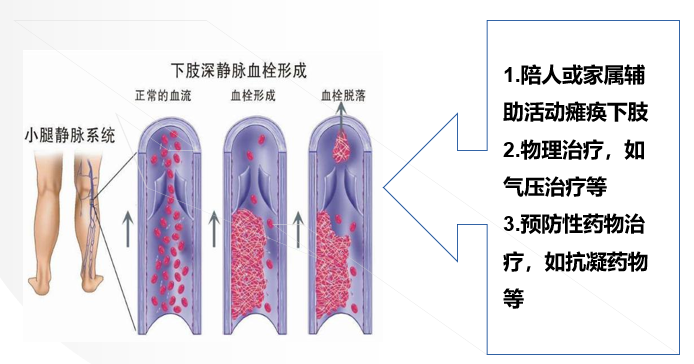

③下肢静脉血栓形成